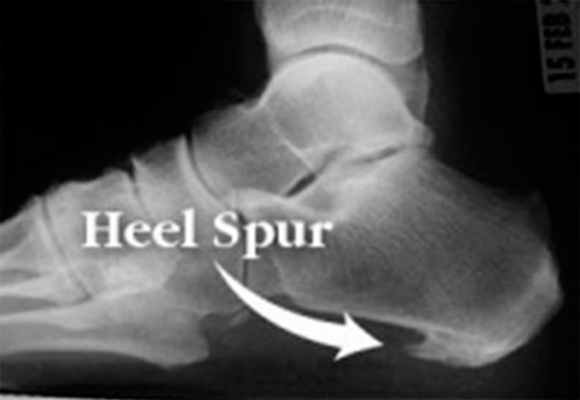

Пяточная шпора представляет собой остеофит пяточной кости. Этиологией шпор является наследственность, нарушения обмена веществ, туберкулез, ревматоидный артрит и системные воспалительные заболевания. К буграм пяточной кости прикрепляется множество мышц и подошвенная фасция, которые оказывают тракционное усилие на кость. Если пяточная шпора располагается на задней поверхности пяточной кости, то это дорсальная пяточная шпора, если она находится по подошвенной поверхности, то это подошвенная пяточная шпора. Дорсальные шпоры часто ассоциируются с тендинопатией ахиллова сухожилия, в то время как подошвенная шпора связана с подошвенным фасциитом. Вершина шпоры находится либо в месте прикрепления фасции на медиальном бугорке пяточной кости, либо в месте прикрепления мышцы короткого сгибателя пальца. Подошвенная фасция во время ходьбы претерпевает постоянное растяжение в связи с ритмичным опусканием и подъемом свода стопы, что приводит к хроническому растяжению апоневроза, которое предрасполагает к воспалительной реакции. Пронация стопы вызывает асимметричное натяжение подошвенной фасции. Избыточная пронация приводит к увеличению натяжения подошвенного апоневроза в месте прикрепления к бугру пяточной кости и считается основным механическим фактором развития подошвенной пяточной шпоры. Хроническая микротравма, которая вызывает разрывы подошвенной фасции вблизи ее прикрепления к кости, приводит к воспалению с дальнейшим развитием оссификации. Пяточная шпора прогрессирует в связи с длительным давлением на подошвенную фасцию и мышцы стопы, или растяжением подошвенной фасции вследствие избыточной подвижности 1 луча. Гиперподвижность структур медиального края стопы дает неравномерность натяжения подошвенной фасции. В области прикрепления фасции к пяточному бугру развивается хроническая микротравма и очаг воспаления, что приводит к развитию фасциита. По мере того, как воспалительный процесс приобретает черты хронического, развивается фиброз и оссификация в области пяточного бугра. Пяточная шпора может протекать либо бессимптомно, либо вызывать боль. Бессимптомные пяточные шпоры встречаются среди нормального взрослого населения в 11% случаев. Большинство пациентов с болью в пятке- это взрослые среднего возраста. У человека под пяткой появляется болезненный участок. Боль, которая локализуется в области медиального бугорка пяточной кости, вызвана давлением на подошву стопы в области прикрепления подошвенного апоневроза к пяточной кости.

Шпоры разделены по характеру течения. Во-первых, это шпоры с незначительной воспалительной реакцией с нечеткими, нерегулярными, неровными контурами с пониженной плотностью кости в области прикрепления подошвенной фасции на рентгенограмме. Они характерны для начала патологического процесса. Во-вторых, это шпоры большого размера, прогрессирование которых связано с весовой нагрузкой. Они протекают бессимптомно в связи с прекращением воспалительного процесса. В-третьих, это большие шпоры, которые вызывают боль в связи с постоянной нагрузкой, вызванной продольным или поперечным плоскостопием, вальгусом пятки и гиперпронацией стопы.

Рис. 7. Рентгенограмма стоп. Пяточная шпора